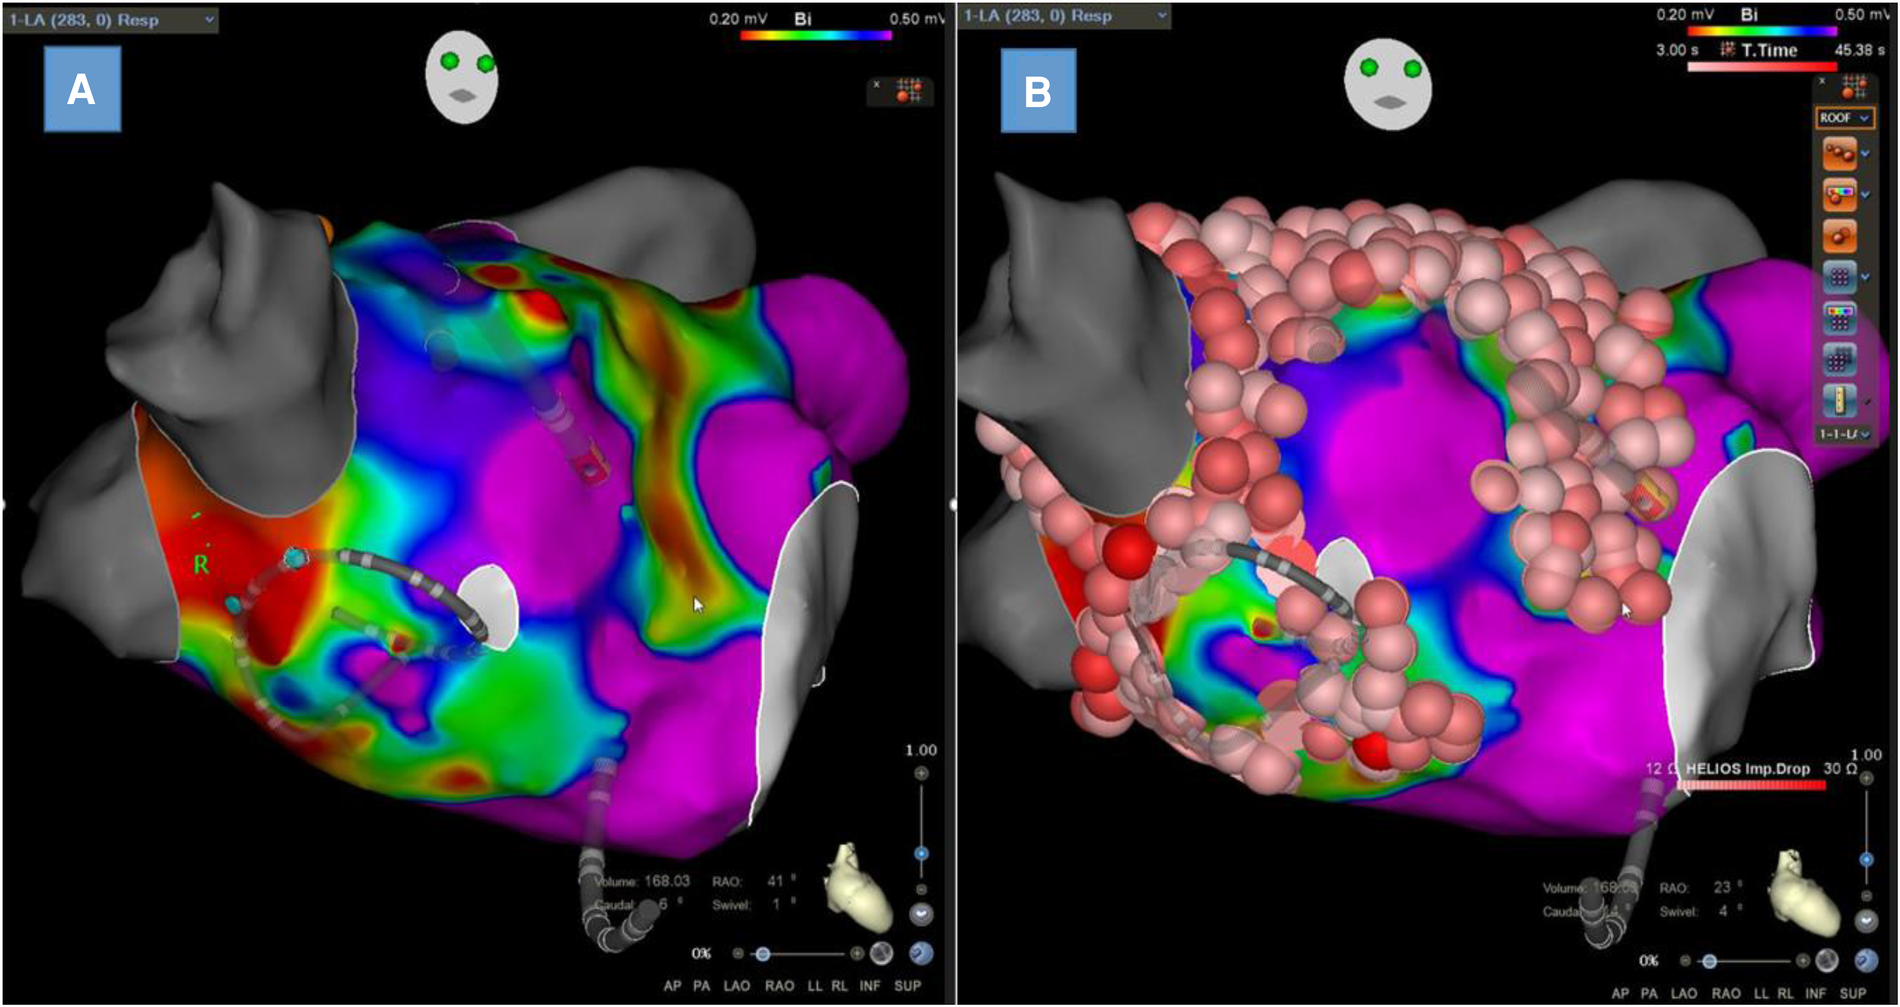

LA voltage mapping

LA endocardial voltage mapping was performed in SR before radiofrequency ablation (Figures 3A,B). Endocardial contact during point acquisition was validated by a stable contact signal for >2 beats. All points recorded in SR were analyzed to exclude mechanically induced premature beats. Any area with an abnormal voltage resulting from inadequate contact between the circular catheter and LA tissue was reanalyzed with a 4-mm irrigated contact-force ablation catheter (ThermoCool® SmartTouch®; Biosense Webster, Diamond Bar, CA, USA, or Tacticath®; Abbott, St Paul, MN, USA). The LA was divided into six anatomical regions: posterior; anterior; septal; lateral; LAA; and inferior. The roof was part of the anterior region as previously described (13). The bipolar voltage amplitude was recorded for every point and within each individual region. The median LA and regional bipolar voltage amplitude measurements were calculated. Left atrial intracavitary volume (LAIV) excluding LAA was obtained for each patient after LA anatomic reconstruction and was expressed in milliliters. The left atrial intracavitary volume index (LAIVI) corresponded to the LAIV indexed to the body surface (expressed in ml m2). LVZ was defined as sites of >3 adjacent low-voltage points with a bipolar peak-to-peak voltage amplitude of <0.5 mV (14) and covering >5% of the LA surface area (LVZ surface/LA surface >5% without LAA orifice, the pulmonary venous antral region, and mitral valve). This threshold value corresponds to the lowest degree of atrial fibrosis detected using LGE-MRI (15). LVZ extent was categorized as stage I (no or discrete LVZ, ≤5%), II (mild, >5% to ≤20%), III (moderate, >20% to ≤35%), and IV (severe, >35%) according to the UTAH fibrosis classification (15). The surface (cm2) of each atrial region and of the LVZ within each atrial region was measured using the 3D-EAM software.

Figure 3

Left atrial bipolar voltage map obtained in sinus rhythm with Lasso™ NAV from Biosense Webster with visualization of low-voltage zones at the anterior wall and septum (A) and the same map with ablation lesions colored in red (B).